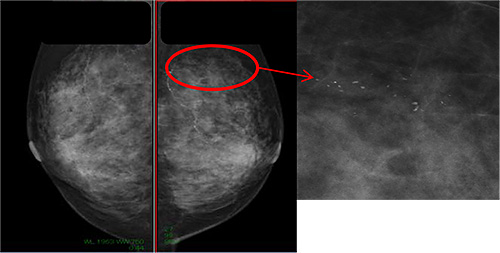

しこりがそれよりも小さい場合は、マンモグラフィー、超音波検査を行わなければわかりません。乳がんを早期に見つけるためには、マンモグラフィー、超音波検査による乳がん検診を行うことが大切です。

図2 マンモグラフィーでのみ分かる病変(小さな石灰化 白い点)